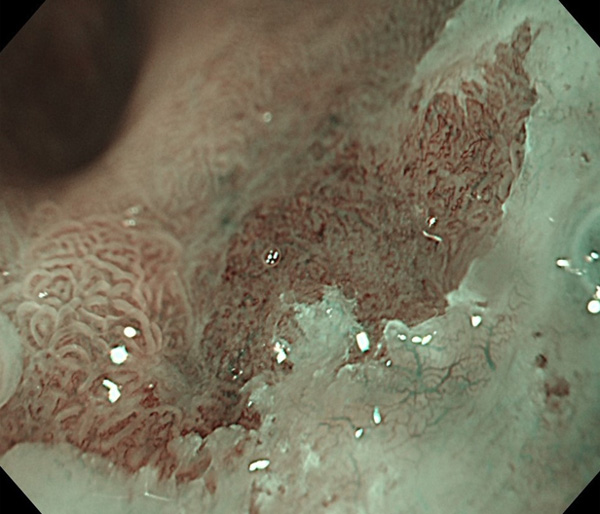

内視鏡所見と病理組織像の1対1対応が可能な症例を公募いたします。主にLSBEに発生した早期癌(HGDを含む)を対象としますが、興味深い症例であればSSBE癌でも結構です。採否は世話人へご一任ください。

症例呈示希望者は応募用紙に記入の上、代表的な内視鏡(2枚)、切除標本(新鮮、固定)、切り出し図、マッピング、代表的組織像とともに、Barrett 食道研究会事務局 barrett.shinshu@gmail.comへお申し込み下さい(10MB以下でお願い致します)。

特に、本邦では極めて稀なlong segment Barrett’s esophagus(LSBE)から発生した早期癌は、診断に難渋する場合も多く、欧米ではランダム生検による検出が標準的とされています。背景のBarrett食道もろとも全体を内視鏡切除+ラジオ波焼灼する欧米と異なり、ESDで内視鏡的な局所切除が基本の本邦では、存在診断+範囲診断(特に水平)を的確に行うことが不可欠です。

そのためには、一流の病理医による組織学的診断とエキスパート内視鏡医による拡大内視鏡像との一対一対応を徹底的に行うことで、『本来、見えないであろう拡大所見の先にある組織構築像が診えてくる』所まで内視鏡診断レベルを上げていく必要があります。その実現には、一対一対応を追究した症例(特にLSBE発生例)1例でも多く経験するしかありません。本研究会でBarrett食道腺癌(LSBE発生早期病変)を共に学び、拡大内視鏡像の一歩先を診るスキルを習得しましょう!一人でも多くの皆様のご参加をお待ちしています。

私は、Barrett食道癌はHGDも含め、内視鏡による存在診断、範囲診断が可能と信じて来ました。しかし最近、NBI拡大観察を併用しても側方範囲診断が不可能なLSBE症例を経験しました。診断技術を向上させるためには、多くの症例を診るしかありません。そこで、Barrett食道に造詣の深い先生方に世話人をお願いし、Barrett食道研究会を立ち上げることに致しました。全国からLSBE症例を集め、内視鏡的、組織学的診断に迫りたいと思います。皆様のご参加をお待ち致します。

2026年1月24日開催の第19回研究会でご提示した検討症例です。 (画像をクリックすると拡大します)